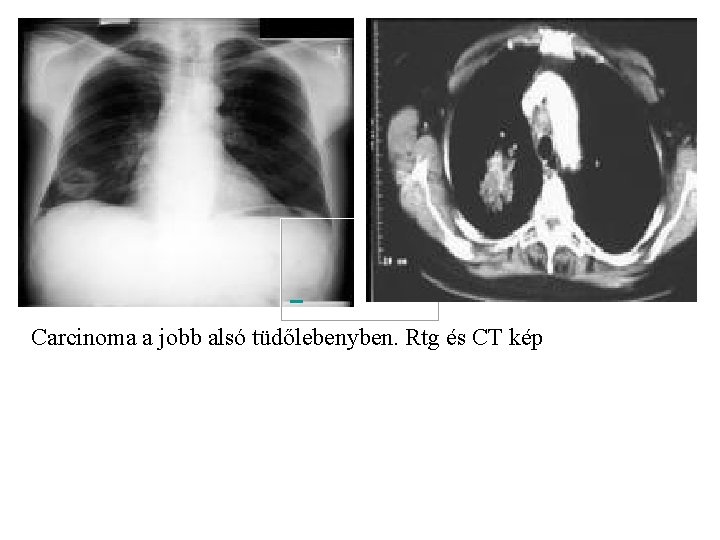

Carcinoma a jobb alsó tüdőlebenyben. Rtg és CT kép